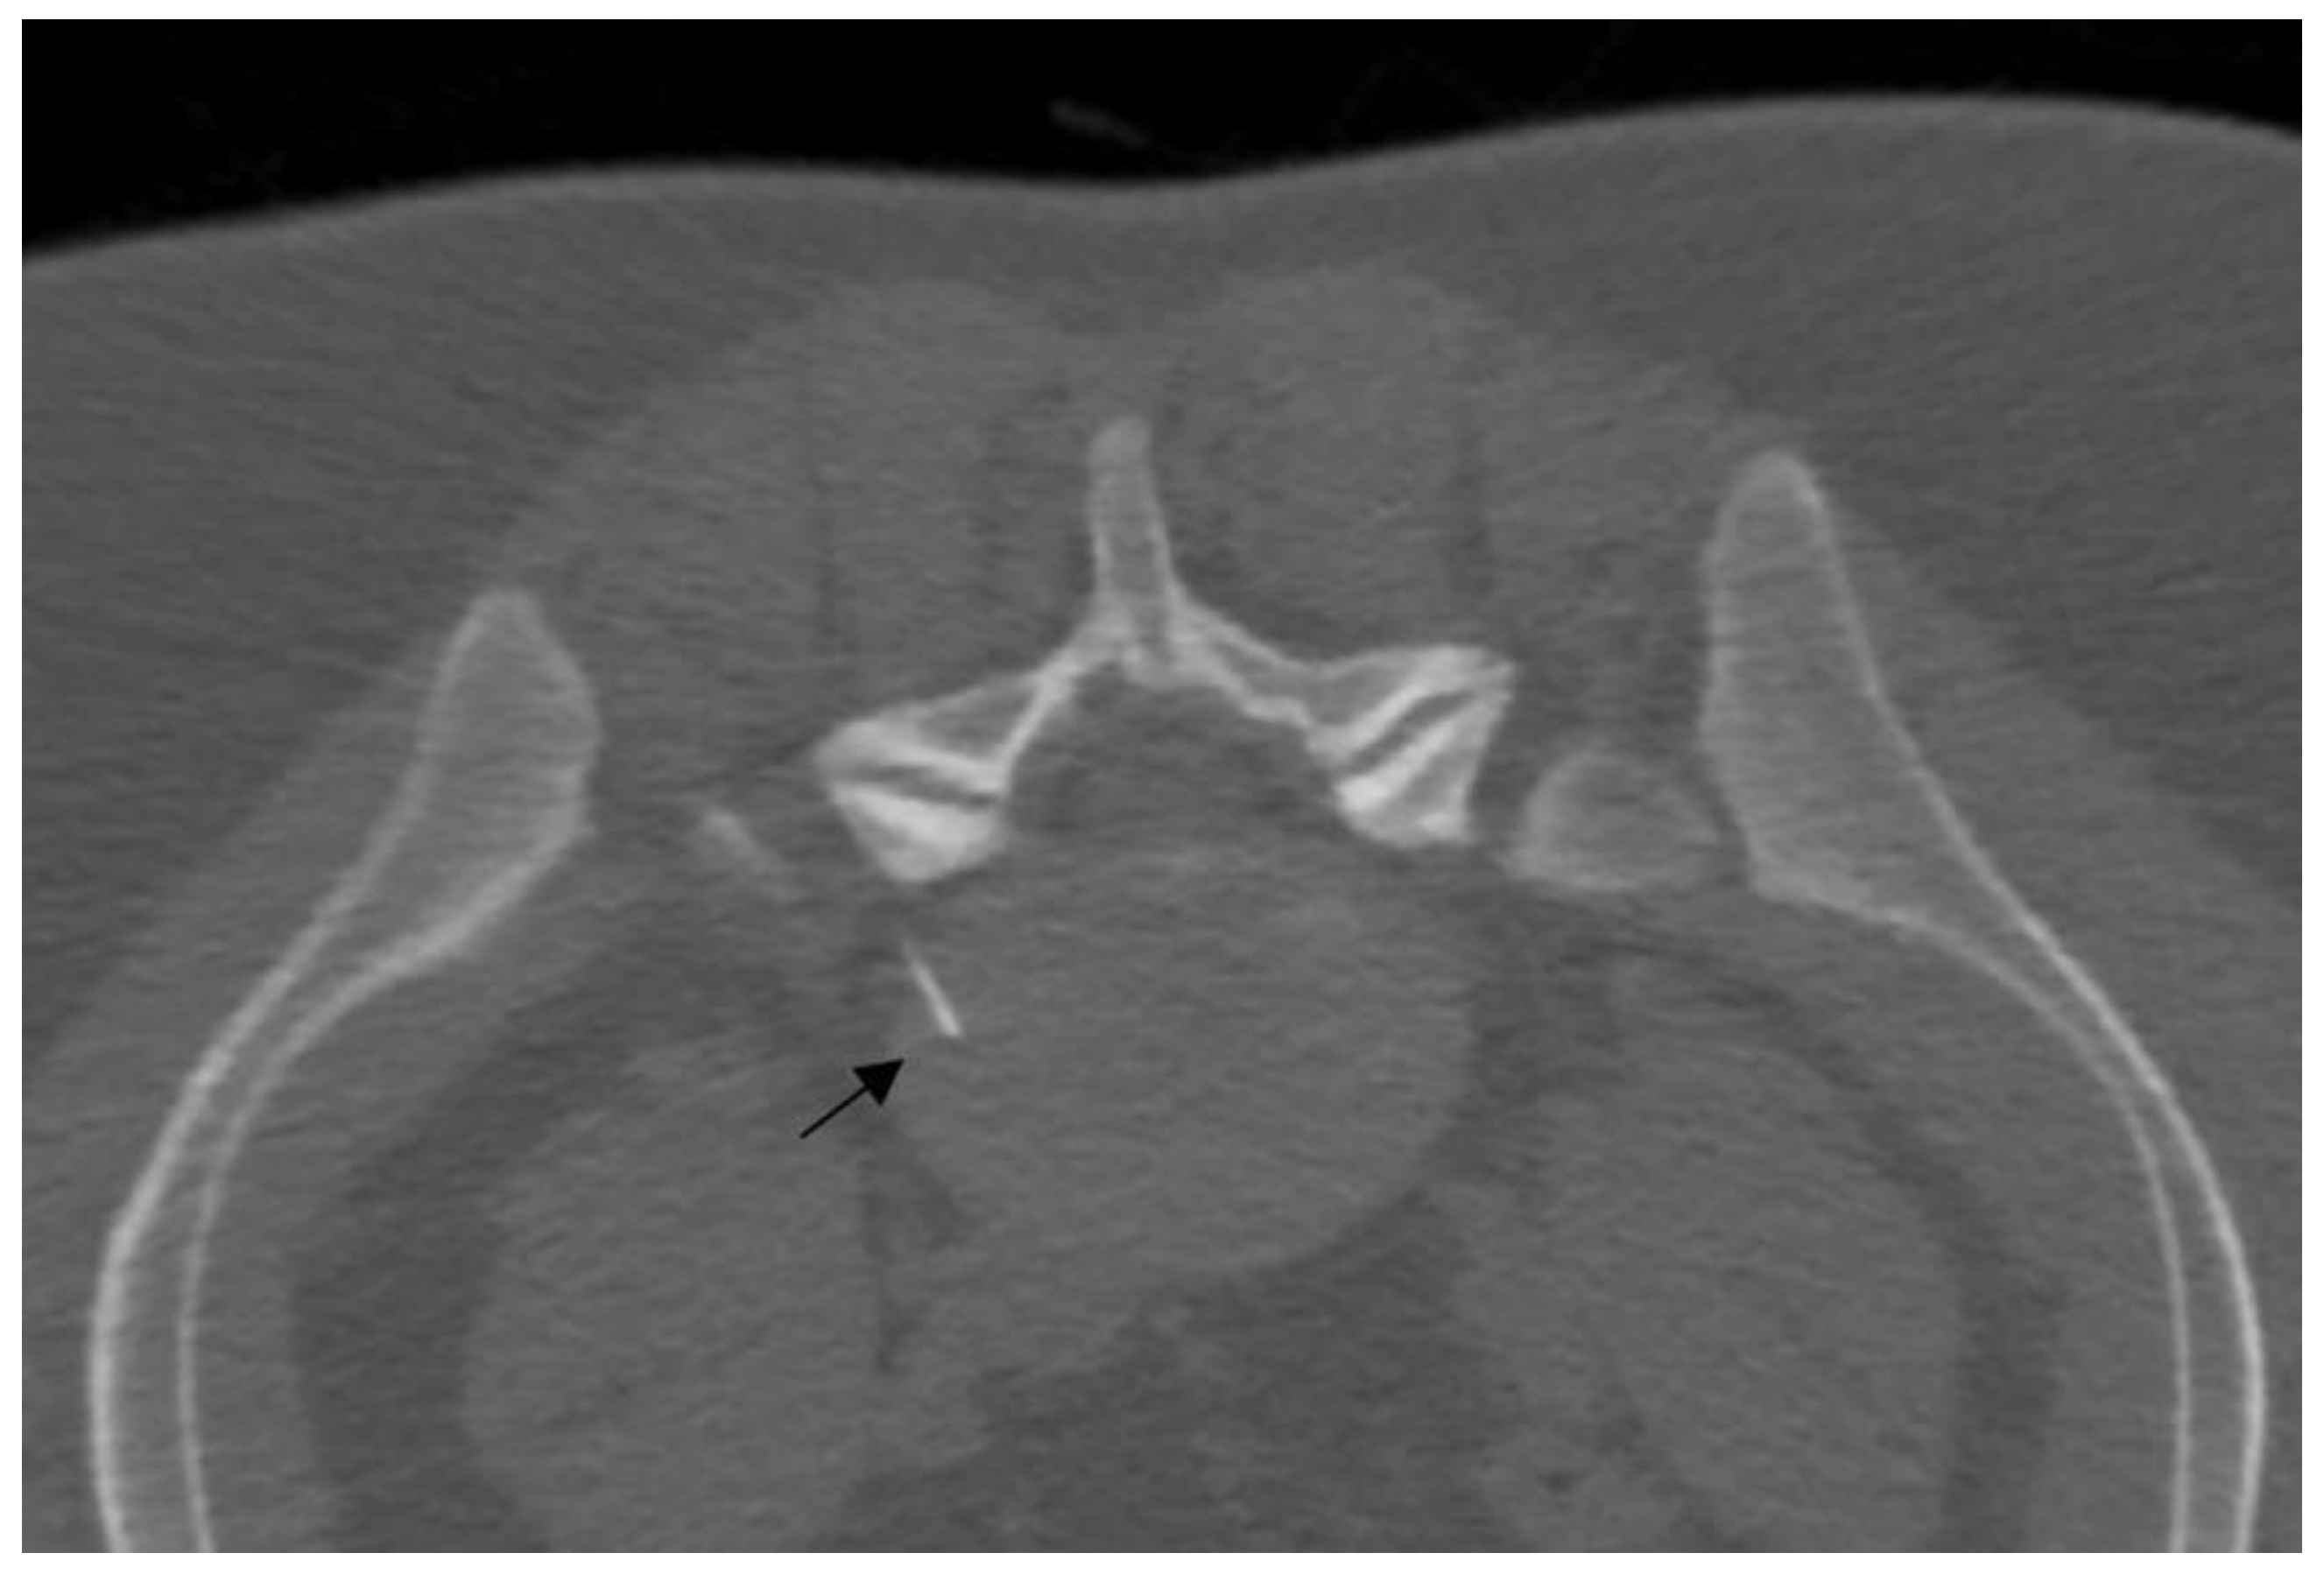

- Napoli, A.; Alfieri, G.; De Maio, A.; Panella, E.; Scipione, R.; Facchini, G.; Albisinni, U.; Spinnato, P.; Nardis, P.G.; Tramutoli, R.; et al. CT-Guided Pulsed Radiofrequency Combined with Steroid Injection for Sciatica from Herniated Disk: A Randomized Trial. Radiology 2023, 307, e221478. [Google Scholar] [CrossRef] [PubMed]

2.4.2. Image-Guided Radiofrequency

Continuous Radiofrequency

Pulsed Radiofrequency